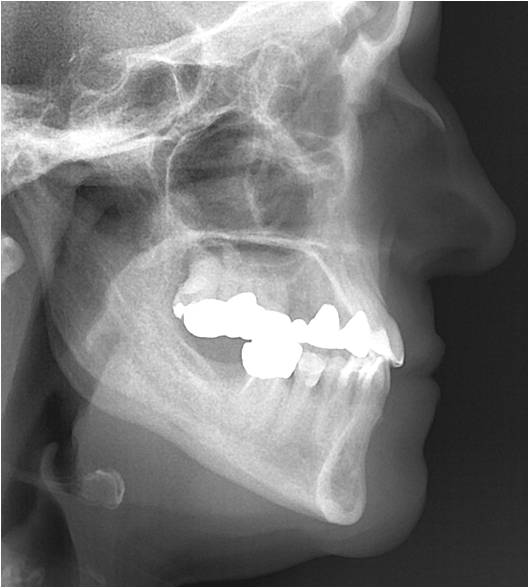

Behandlungsverlauf mit Fernröntgenseitenbilder

Im Fernröntgenseitenbild ist sichtbar, dass die Profilverbesserung der Patientin durch Retrusion der Unterkiefer Front erreicht wurde. Sehr interessant hierbei ist folgender Zusammenhang:

In Behandlung der Progenie

Nach Behandlung der Progenie

Jeder Mensch neigt dazu, sein Gesicht in der frontalen Ebene, achsengerecht d. h. im Lot, von Oben nach Unten, gerade zu stellen. So ist es typisch, dass Patienten mit einem Rückbiss das Kinn eher nach Vorne schieben und die Stirn eher nach hinten geneigt ist. Umgekehrt verhält sich der Patient mit Vorbiss (Progeniepatient) so, dass er den Kopf eher nach vorne unten neigt um wieder eine gerade Stellung des Gesichts zu erhalten. Diese unterschiedliche Neigung des Kopfes, hat einen erheblichen Einfluss auf die Atemwege! Der nach vorne geneigt Kopf verengt die Atemwege und der nach hinten geneigte Kopf öffnet die pharyngialen Atemwege. Durch die neue Kieferrelation, hat diese Patientin trotz Retrusion der Unterkiefer Front eine Verbesserung des respiratorischen Traktes mit Vergrößerung des Mesiopharynx erreicht.